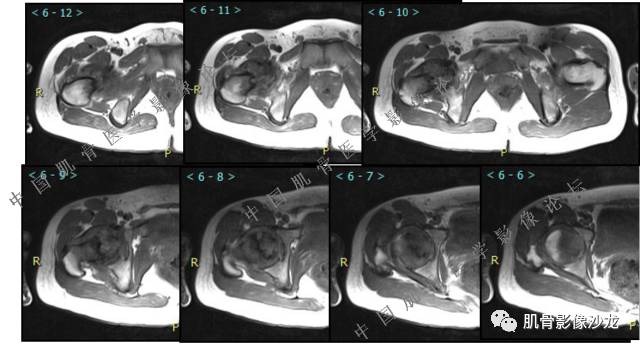

主诉:右髋及右膝部疼痛3月余

现病史:3月前打球时自觉右大腿肌肉拉伤后右髋及右膝部疼痛,自服“活血化瘀”类药物(具体不详)后自觉疼痛缓解,2月前打球时再次扭伤,右髋及右膝部疼痛明显,行走时疼痛加重,自服药物治疗,效果不佳,遂来诊。

葛英霖 20:10 判断恶性程度需要看骨髓内浸润的是肿瘤还是水肿 ,从目前看,骨肉瘤是要考虑的

张小林 20:13 磁共振有双低信号,结合CT确实要考虑有纤维成份。

葛英霖 20:23 @张时秒 晋江市安海医院 影像科 t1上看异常信号的边界

夏威夷的风 20:15 T1WI

Echo 20:23 我个人觉得,17岁男性,病灶发生在原干骺端区域,溶骨性骨质破坏,似有肿瘤骨,有软组织肿块形成,从常见病发生率来说,骨肉瘤还是要考虑的

葛英霖 20:24 这个部位有一个需要鉴别的就是软骨母